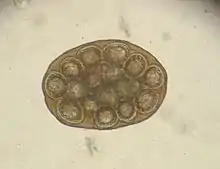

Dipylidium life cycle

Adult morphology

The adult worm is about 18 inches (46 cm) long. Gravid proglottids containing the worm's microscopic eggs are either passed in the definitive host's feces or may leave their host spontaneously and are then ingested by microscopic flea larvae (the intermediate hosts) in the surrounding environment. As in all members of family Dipylidiidae, proglottids of the adult worm have genital pores on both sides (hence the name double-pore tapeworm). Each side has a set of male and female reproductive organs. The uterus is paired with 16 to 20 radial branches each. The scolex has a retractable rostellum with four rows of hooks, along with the four suckers that all cyclophyllid cestodes have.